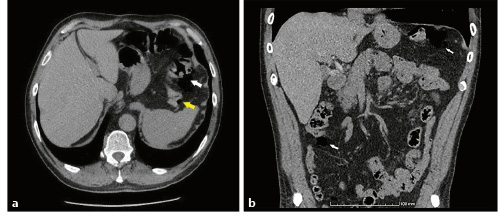

Fig. 3 a, b Abdominopelvic CT scan, axial section (a) and coronal section (b). Pneumoperitoneum and air bubbles adjacent to the lumen of the bowel (white arrows), some of them in subserosal location (yellow arrow).

A 51-year-old man, former smoker (20 pack-years), with hemorrhoidal disease, irritable bowel syndrome, pulmonary emphysema and a mechanical prosthetic aortic valve under warfarin, presented for post-polypectomy surveillance colonoscopy. He complained of frequent tenesmus, diarrhea (2-3 liquid dejections in the morning), bloating and abdominal discomfort. Several polypoid grape-like submucosal masses were identified in a 10-cm segment of the descendent colon (Fig. 1a, b). Since the lesions were easily indented with gentle pressure and had a bluish hue, pneumatosis cystoids intestinalis (PCI) was suspected. Biopsy of one of these masses caused immediate deflation, confirming the diagnosis. Histopathological evaluation showed normal crypt architecture and a congestive edematous lamina propria with minimal inflammatory infiltrate suggesting reactive changes (Fig. 2). The patient had no history of abdominal trauma and no pharmacological (alpha-glucosidase inhibitors, steroids) or infectious (Clostridioides difficile, tuberculosis, human immunodeficiency infection) causes. Over a long-term follow-up of 12 years, the mild symptoms were managed conservatively with loperamide, spasmolytics and probiotics, which showed an improvement. In this period, two surveillance colonoscopies were performed showing the same unchanged endoscopic findings described above. Recently, due to surveillance of an ascending aortic aneurysm, a contrasted chest computed tomography (CT) identified a small pneumoperitoneum in the left subphrenic region. Abdominal CT extension showed more free peritoneal air in the left hypochondrium and air bubbles adjacent to the lumen of the bowel, some of them being subserosal (Fig. 3a, b).